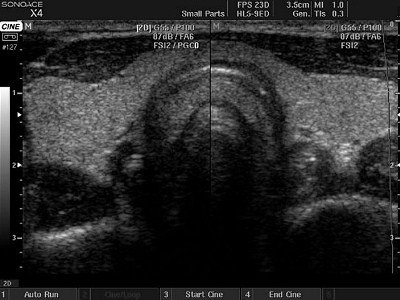

УЗИ щитовидной железы

УЗИ щитовидной железы.jpg(женщины страдают чаще мужчин, в соотношении 3:1). Среди онкологических заболеваний злокачественные опухоли щитовидной железы составляют до 3%.

Ультразвуковая диагностика имеет почти 100% чувствительность в выявлении очаговых поражений щитовидной железы, в выявлении рака около 93%. Важно своевременно выявить различные пограничные патологические состояния, влекущие развитие диффузно-токсического зоба, аутоимунного тиреоидита, опухолевых процессов.

При УЗИ щитовидной железы выявляются:

- аномалии развития (положения и размеров),

- гиперплазия (диффузная и узловая форма),

- тиреоидиты (острые и хронические),

- аденомы (доброкачественная опухоль),

- злокачественные опухоли,

- патология паращитовидных желез.